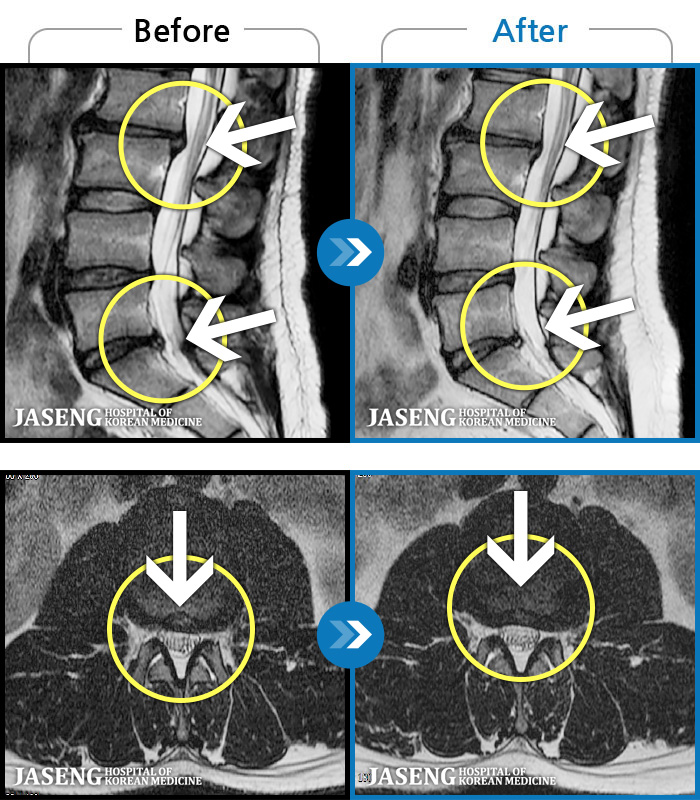

- MRI ġ

MRI ġ

1,304 MRI ũ ʸ Ȯϼ.

Ƹ ϰ ־.